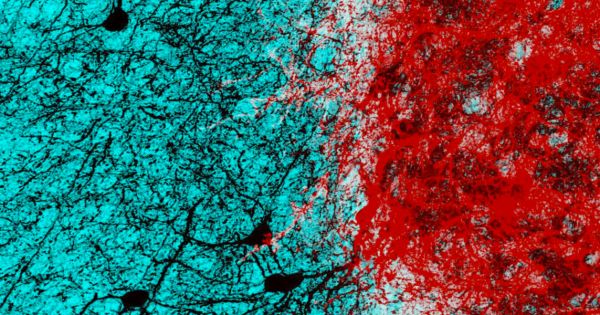

Bilimde Bugün: Korku hissini azaltmanın yolu bulundu!